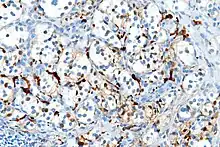

With immunohistochemistry, the chief cells located in the cell balls are positive for chromogranin, synaptophysin, neuron specific enolase, serotonin, neurofilament and Neural cell adhesion molecule; they are S-100 protein negative. The sustentacular cells are S-100 positive and focally positive for glial fibrillary acidic protein. By histochemistry, the paraganglioma cells are argyrophilic, periodic acid Schiff negative, mucicarmine negative, and argentaffin negative.

S100 immunostain highlighting the sustentacular cells in a paraganglioma